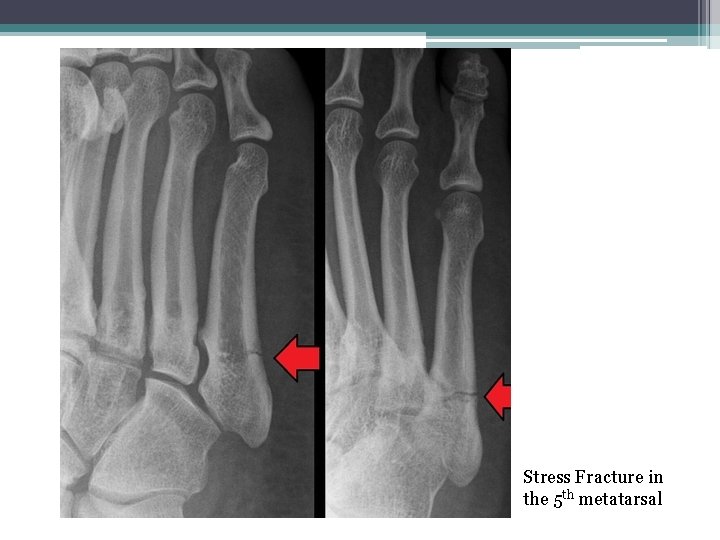

• 9 - Stress Fracture: A bone breaks because of repeated stresses and strains, more common among athletes.

Stress Fracture in the 5 th metatarsal